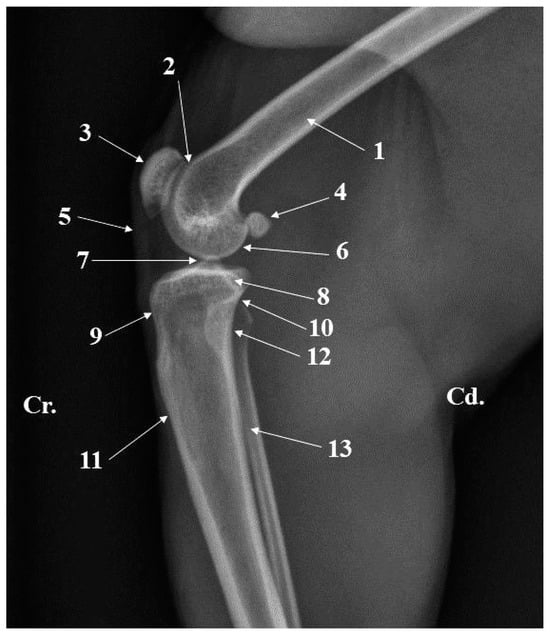

Figure 6. Stifle joint radiograph—medio-lateral projection. 1. Femur; 2. Femoral trochlea; 3. Patella; 4. Sesamoid bone of gastrocnemius; 5. Patellar ligament; 6. Femoral condyle; 7. Intercondylar tuberosity; 8. Medial condyle of the tibia; 9. Tibial tuberosity; 10. Proximal tibio-fibilar joint; 11. Tibial tuberosity; 12. Head of fibula; 13. Body of fibula.

The radiographs of the thigh area of the cranio-caudal and caudo-lateral projections were very helpful. These images provided information related to the position, presence, and size of the anatomical features of the proximal and distal epiphysis. Structures such as the greater trochanter, lesser trochanter, intertrochanteric crest, and subtrochanteric fossa could be easily observed at the level of the proximal epiphysis of the femur (Figure 3 and Figure 4). The more delicate structures of this extremity, such as the gluteal tuberosity, linea aspera and linea pectinea, were not identifiable. For the distal epiphysis, the radiographic imaging confirmed the presence of the sesamoid bones of gastrocnemius muscles—two round bony structures located caudal and proximal from thefemoral condyles (Figure 6).

The radiographic investigation of the crural region allowed the identification of the articular elements of the proximal and distal ends of the tibia and fibula and facilitated the identification of the tibiofibular interosseous space (Figure 6 and Figure 11), but it was difficult to identify small structures such as the malleolar groove.